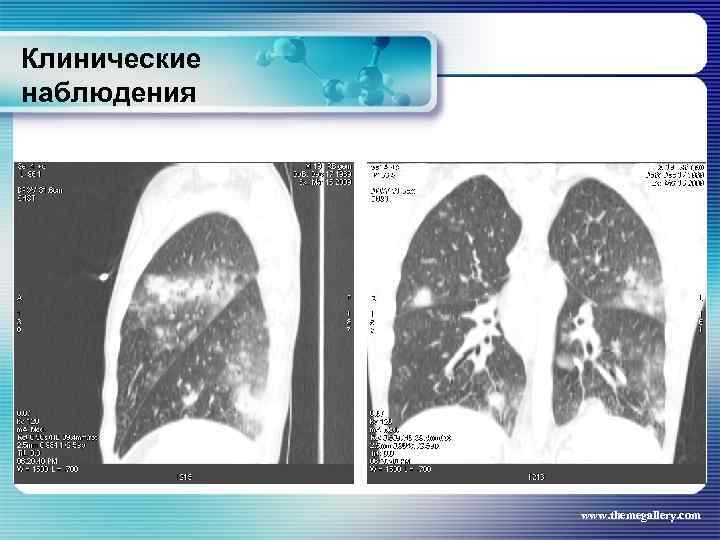

Клинические наблюдения Тот же пациент Был сформулирован клинический диагноз: Лифома Ходжкина, нодулярный склероз IV B стадия с поражением шейных, надключичных, подчелюстных, подмышечных, переднегрудных, парастернальных, паховых, внутригрудных, абдоминальных лимфатических узлов, печени, костного мозга, позвонков. В связи с выраженной нарастающей интоксикацией была начата терапия преднизолоном и первый цикл ВЕАСОРР. на этом фоне появились: резко повышенные показатели трансаминаз, асцит, массивные белковые отёки, сохранилась опухолевая интоксикация. Развилась аплазия гемопоеза. Доза преднизолона была увеличена. На этом фоне развилась полисегментарная грибковая пневмония. www. themegallery. com

Клинические наблюдения Тот же пациент Был сформулирован клинический диагноз: Лифома Ходжкина, нодулярный склероз IV B стадия с поражением шейных, надключичных, подчелюстных, подмышечных, переднегрудных, парастернальных, паховых, внутригрудных, абдоминальных лимфатических узлов, печени, костного мозга, позвонков. В связи с выраженной нарастающей интоксикацией была начата терапия преднизолоном и первый цикл ВЕАСОРР. на этом фоне появились: резко повышенные показатели трансаминаз, асцит, массивные белковые отёки, сохранилась опухолевая интоксикация. Развилась аплазия гемопоеза. Доза преднизолона была увеличена. На этом фоне развилась полисегментарная грибковая пневмония. www. themegallery. com

Клинические наблюдения Тот же пациент Антибактериальная терапия была не эффективна, на фоне противомикробной терапии (вифендом) достигнут положительный эффект, больной переведен на другую программу химиотерапии (ABVD) www. themegallery. com

Клинические наблюдения Тот же пациент Антибактериальная терапия была не эффективна, на фоне противомикробной терапии (вифендом) достигнут положительный эффект, больной переведен на другую программу химиотерапии (ABVD) www. themegallery. com